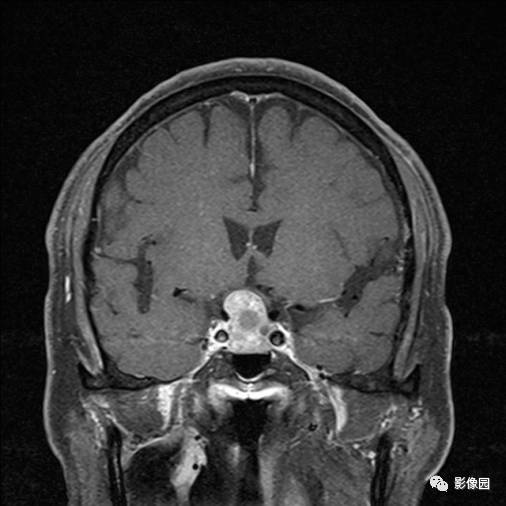

【病例】垂体瘤合并出血1例MR影像表现

独孤求败:诊断为垂体瘤,蝶鞍扩大,鞍底下陷,鞍内见突向鞍上生长的团块状异常信号,T1WI呈等及稍高信号,T2WI呈等及低信号,增强扫描病灶呈明显不均匀强化;垂体柄显示不清,视交叉受压上抬。

bnzhang07:这是典型的垂体大腺瘤,垂体大腺瘤冠状扫描显示肿瘤呈哑铃状或“束腰征”,这是由于肿瘤伸于鞍上,中部受鞍隔束缚的原因。

lovethemoon:这不是颅咽管瘤,而是垂体瘤,颅咽管瘤时可见正常的垂体结构,此患者看不到正常的垂体结构,病变内短T1短T2异常信号是出血,垂体瘤合并了出血,颅咽管瘤囊变时的信号一般是长T1长T2。

【答案】垂体瘤合并出血